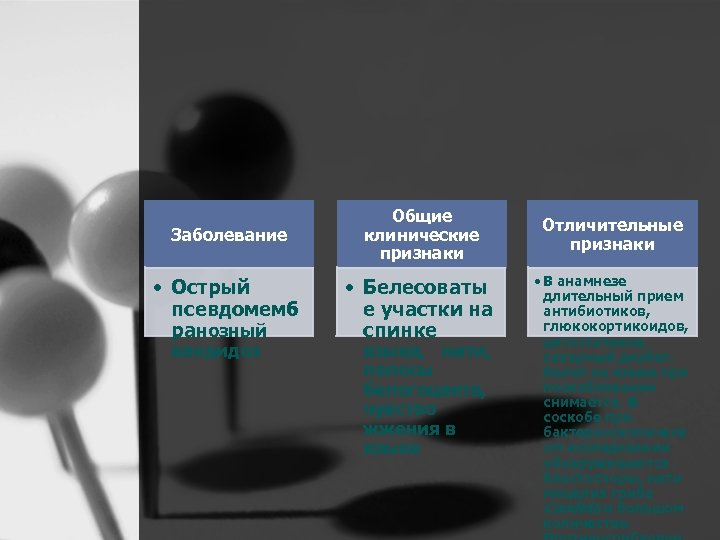

Заболевание Общие клинические признаки • Острый псевдомемб ранозный • Белесоваты е участки на спинке кандидоз языка, нити, полосы белогоцвета, чувство жжения в языке Отличительные признаки • В анамнезе длительный прием антибиотиков, глюкокортикоидов, цитостатиков, сахарный диабет. Налет на языке при поскабливании снимается. В соскобе при бактериоскопическ ом исследовании обнаруживаются бластоспоры, нити мицелия гриба Candida в большом количестве.